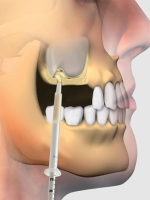

ایمپلنت فول فک

در مرکز تخصصی دکتر حامد محمودی، تمام خدمات زیبایی صورت، جراحی و ایمپلنت را با بالاترین استاندارد جهانی تجربه میکنید. ما یک مرکز تمام دیجیتال هستیم؛ از اسکن سهبعدی تا طراحی لبخند و انجام جراحیها، همه مراحل با پیشرفتهترین تکنولوژیها انجام میشود.

your smile reaches perfection through the precision of digital dentistry and the art of dental aesthetics